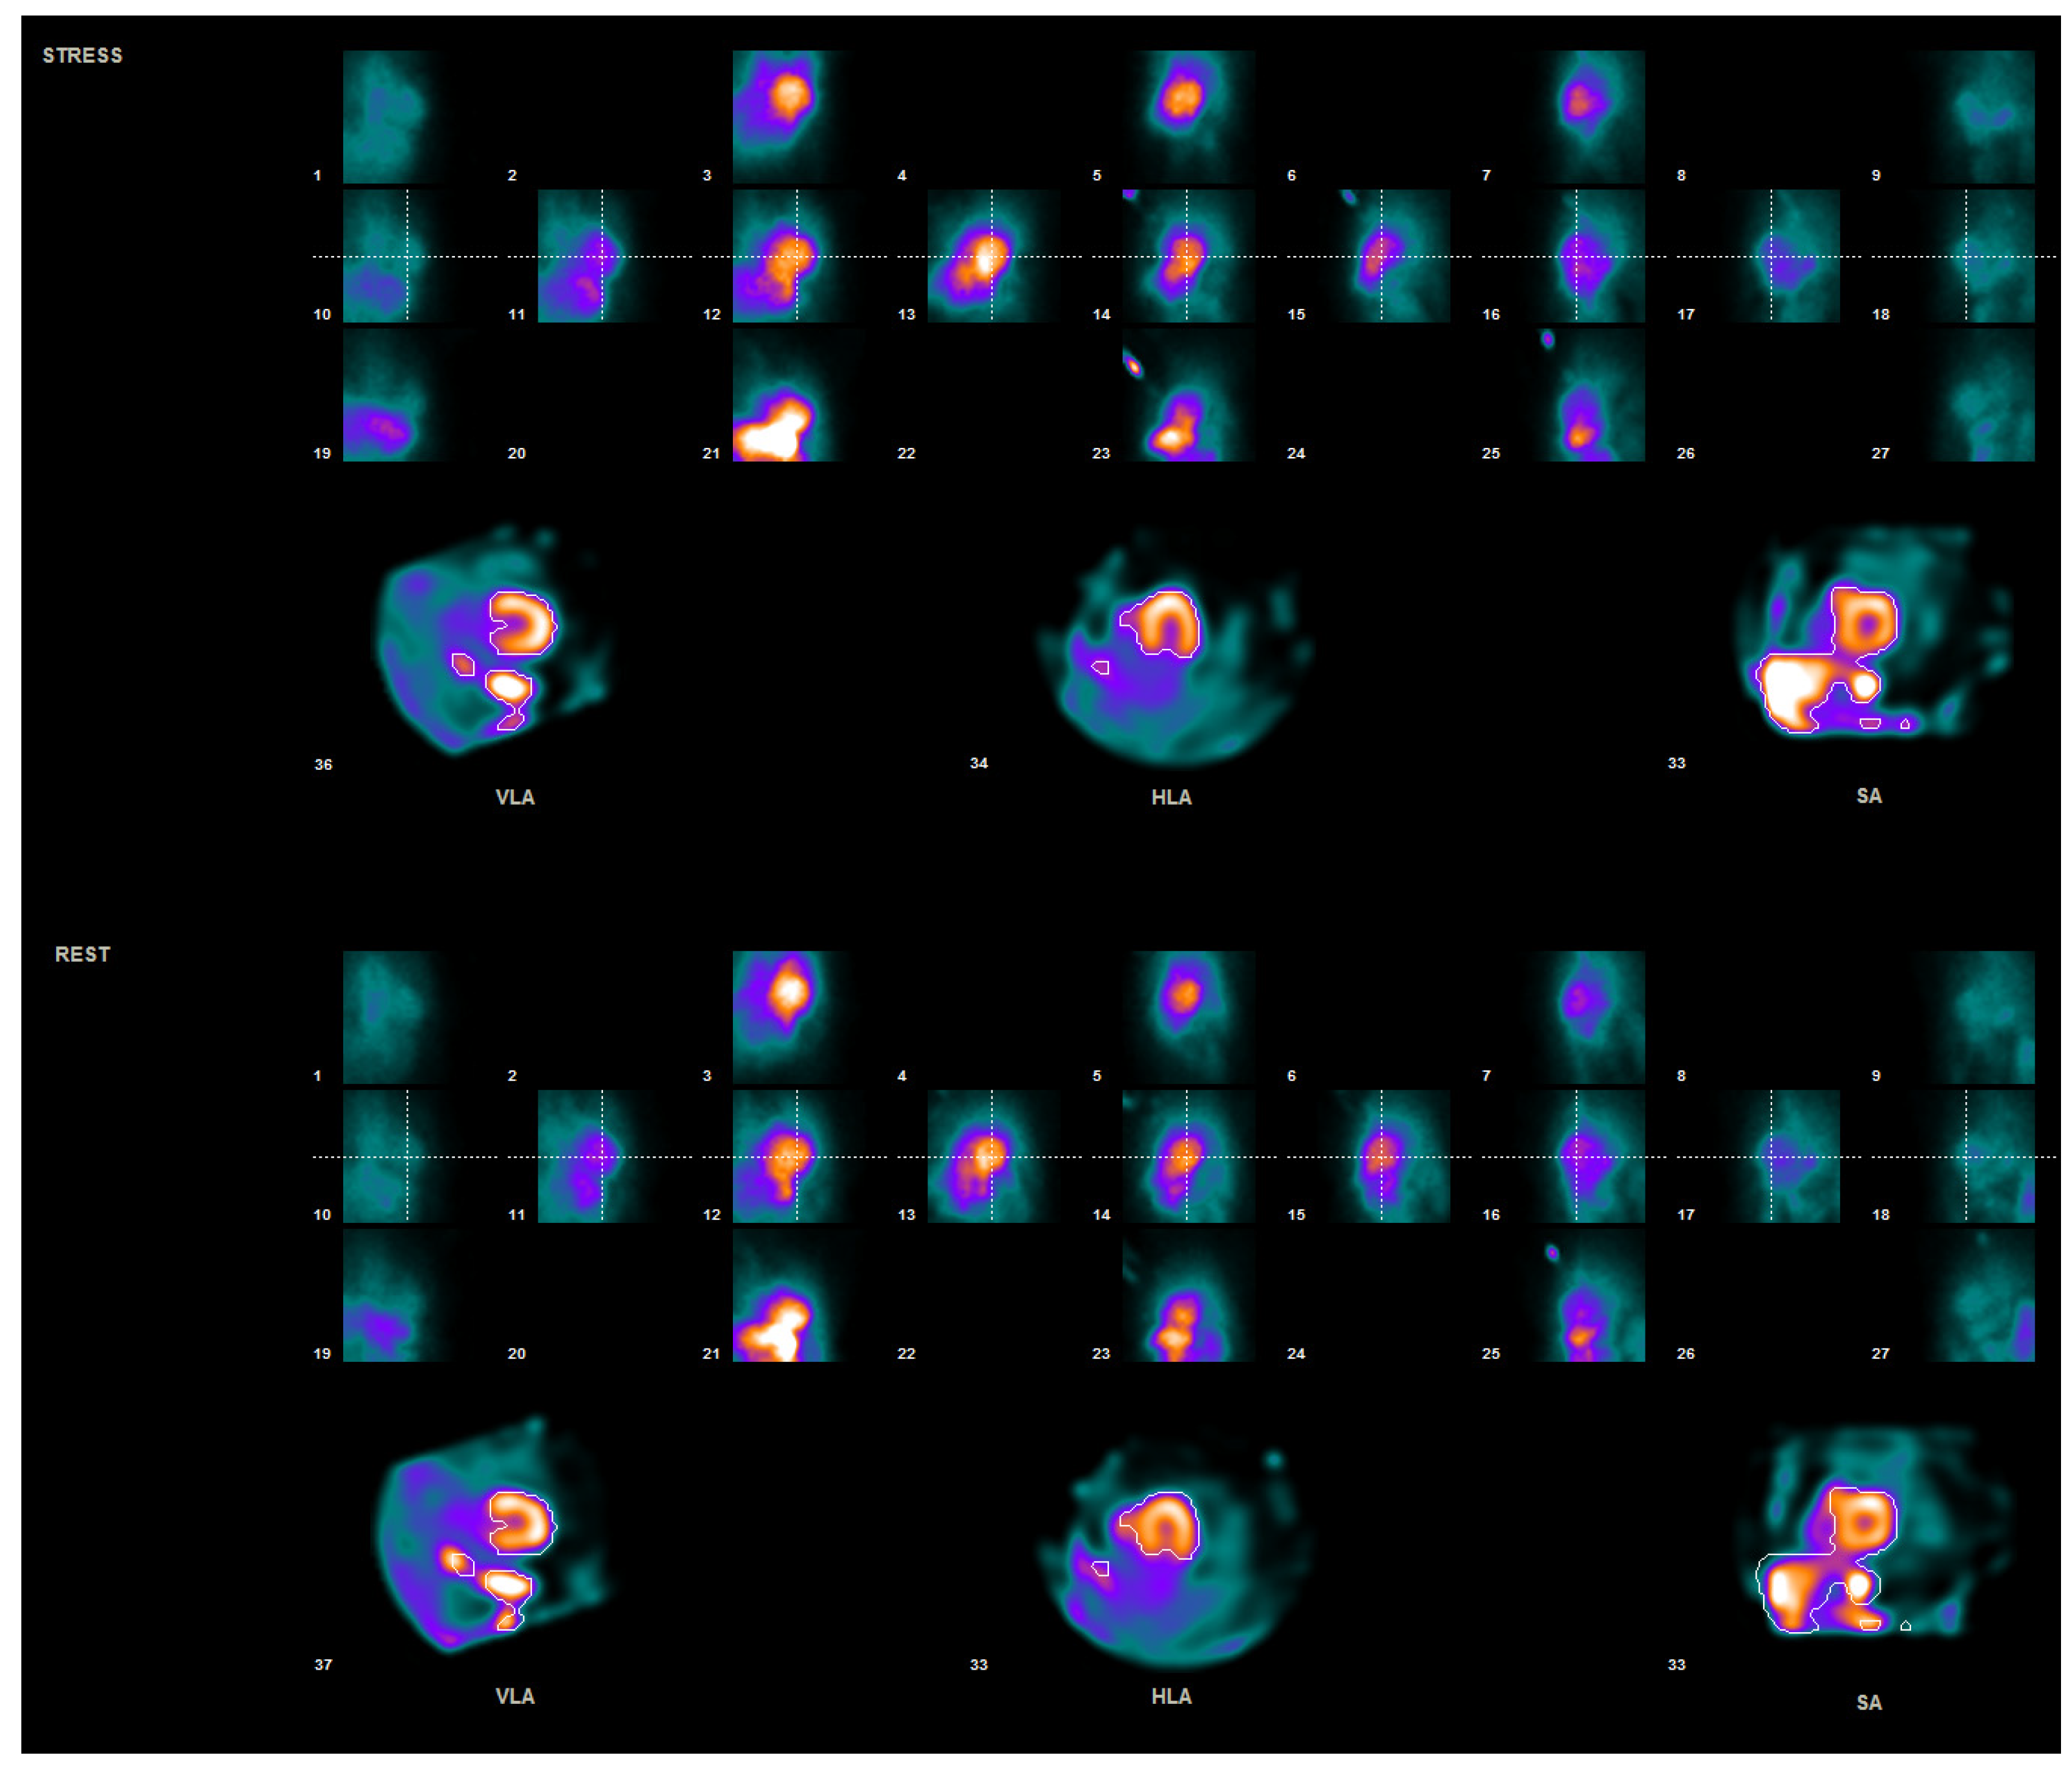

2. Materials and Methods

2.1. Patient Preparation and Data Acquisition

2.2. Data Processing